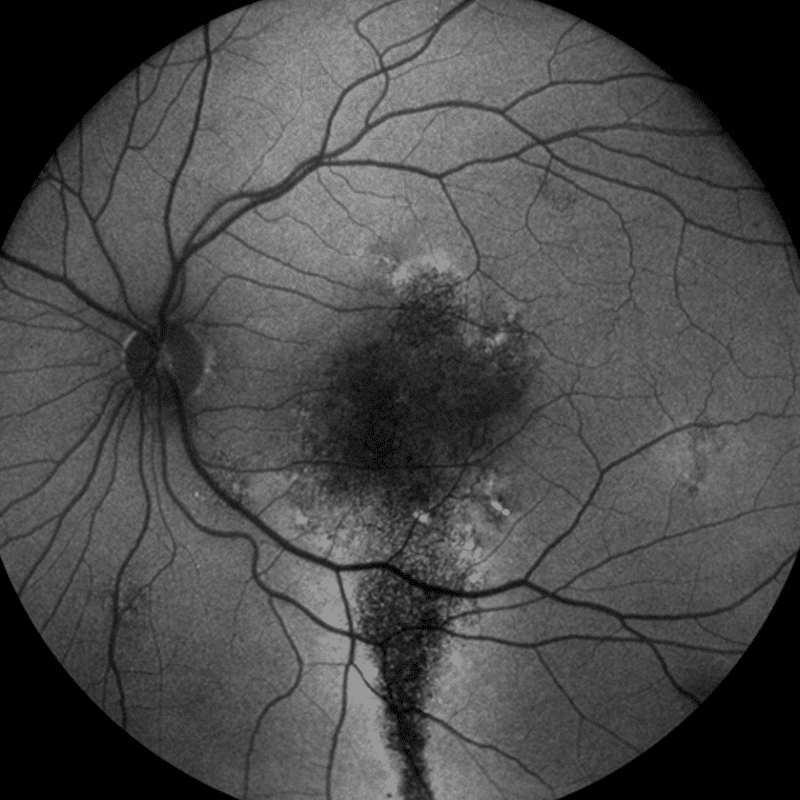

- Autofluorescence allows a look at the RPE (Retinal Pigment Epithelium) layer integrity

Not only does the EIDON AF have a fantastic range of imaging modalities at its disposal, it also offers high-quality, crisp widefield imaging. It can achieve up to 110° thanks to the unique mosaic functionality. This widefield image function is available for all of its imaging modalities. Widefield imaging is crucial in diagnosing pathologies that may initially present in the periphery.

Unsurpassed quality in retinal imaging

The confocal nature of this device enables highly detailed and sharp contrast autofluorescence images. This is achieved in one shot and does not use image averaging. In addition, it is able to scan through cataract and other media opacities.